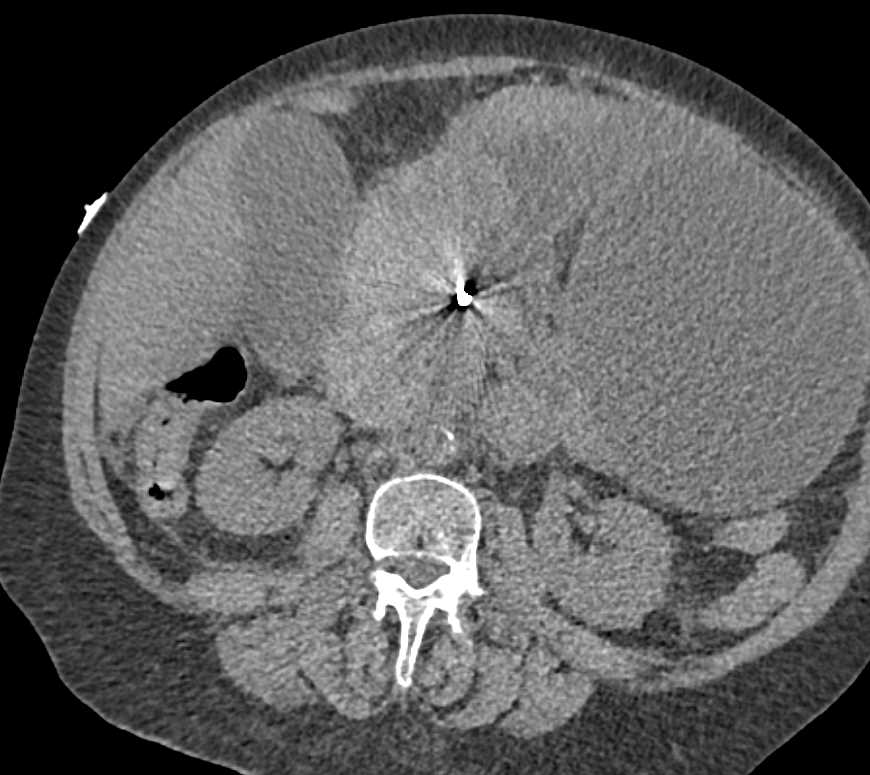

Small Bowel Ischemia